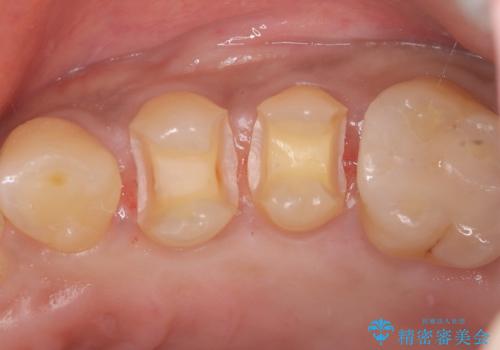

- 前医で治療された詰め物の部分に、定期検診で虫歯が見つかったため、セラミックインレーにて修復治療を行いました。

接着時にはラバーダム防湿を行っています。